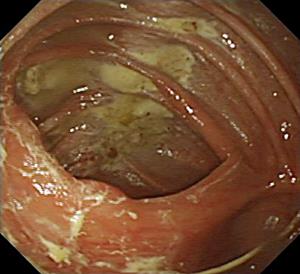

内視鏡という器械で腸内を覗いてみますと、きれいなピンク色で、思わ ず触ってみたくなるほどです(左図)。

イメージとしては大腸イコール大便でしょうが、きちんと下剤で洗浄しま すと、臭いは全くなく、消化液などがないために、胃袋よりは数段もきれ いな色・形をしております。 輪状のヒダがあり、表面(腸の内側で粘膜 といいます)は滑らかで、血管が透けてみえるのが健常者腸の所見で す(綺麗でしょう)。

腸に炎症がおきますと、ヒダがなくなったり、粘膜がゴツゴツしたり、赤 く腫れてきたりして、血管網が見えなくなります。 充血や出血さらには 潰瘍が起こることもあります。